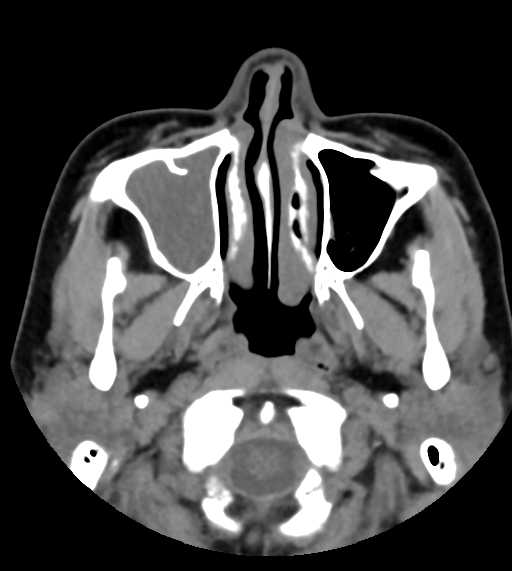

CT検査

内科領域

頭部

その他の領域

その他

副鼻腔炎